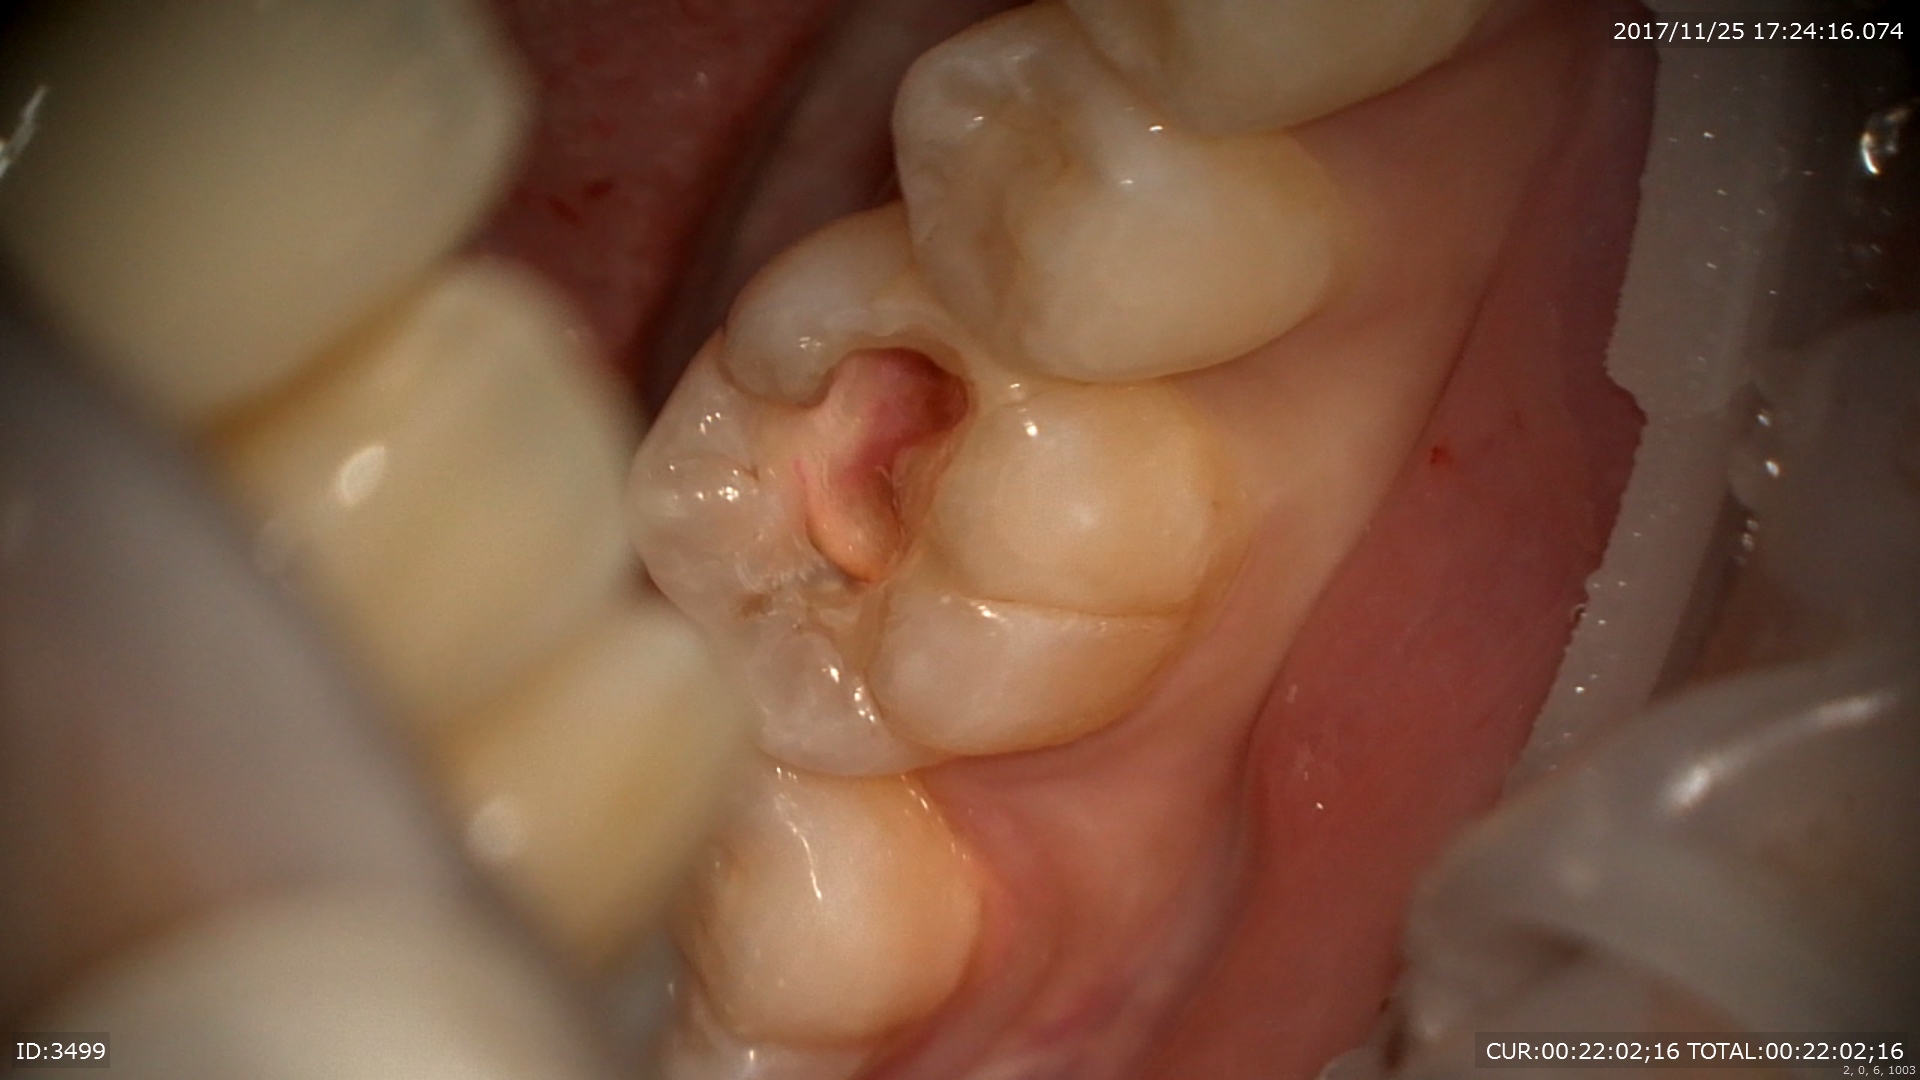

ケース2:歯髄(神経)温存処置 主訴;他院で不安になった。神経を取られるかも。

右下6番。確かに深い。でも詰め物に隙間がある。治療がずさん。。。

そこでまずマイクロスコープで詰め物を除去

やっぱり感染源の取り残し。。

神経に触れそうなところは間接覆髄(MTA)

象牙質の再生を促します。

暫間修復